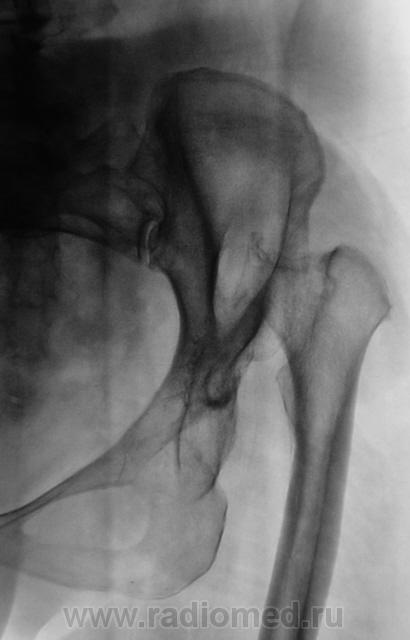

Пол пациента: Женский пол Тип патологии: Врожденная патология Область исследования: Скелетно-мышечная система Методы исследования: Rg С рождения... https://radiomed.ru/sites/default/files/styles/case_slider_image/public/user/12/2.pb130018_0.jpg?itok=whTfL_-m https://radiomed.ru/sites/default/files/styles/case_slider_image/public/user/12/3.pb130018a.jpg?itok=bxJZhidK ID:20367 Сб, 31/03/2012 - 08:39 #1 Santuus Не на сайте Был на сайте: 2 года 10 месяцев назад Зарегистрирован: 01.07.2009 - 23:08 Публикации: 109 Не диагносцированный вывих бедра с образованием неоортроза.

Не диагносцированный вывих бедра с образованием неоортроза.